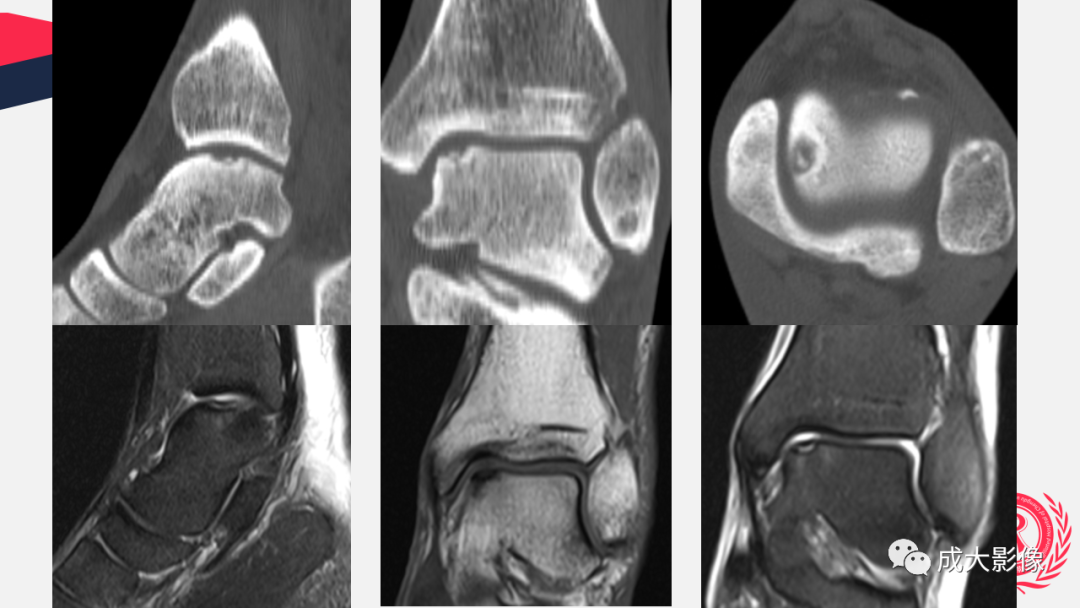

【PPT】剥脱性骨软骨炎-2